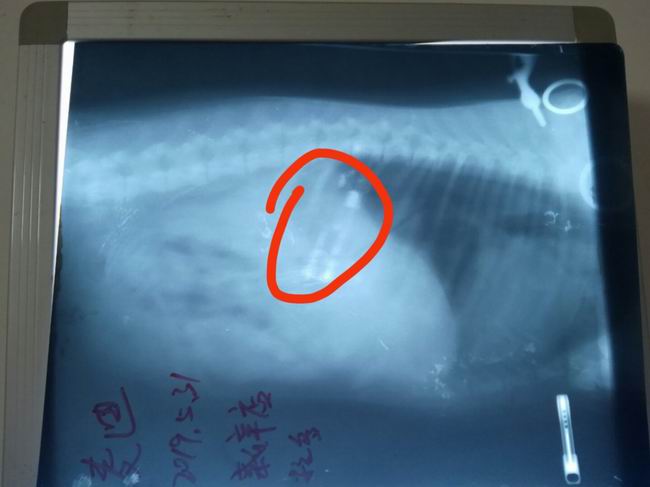

拉布拉多麥迪誤吞入打火機,主人來我院進行治療,經(jīng)過x光檢查,異物(打火機)在胃內(nèi)清洗可見,初步通過藥物促使異物排出,若不能自主排出需要進行手術(shù)取出異物。